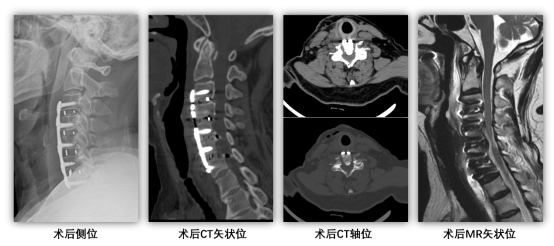

术后恢复效果立竿见影,四肢麻木症状快速缓解,困扰许久的腰腹部束带感完全消失;次日即可下床活动,行走不稳、踩棉感显著改善,肢体力量逐步恢复。复查影像椎管减压效果显著,脊髓顺利膨隆,手术达到预期治疗目标。